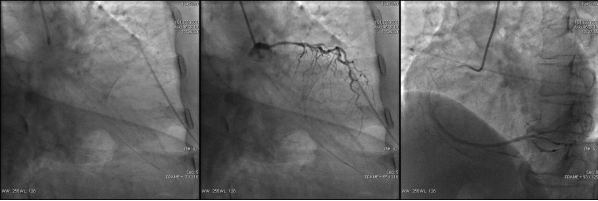

冠脉造影

造影时间: 入院第19天。

造影结果(一): LAD:中远段狭窄30%~40%,较长病变。LCX:中段狭窄80%~85%。

![]()

造影结果(二): RCA:近段狭窄85%~90%。

造影结论及应对策略: LAD:中远段狭窄30%~40%,较长病变。LCX:中段狭窄80%~85%。 RCA:近段狭窄约85%~90%。造影后向患者家属交代病情,与家属沟通后决定择期行介入治疗。

第一次手术过程

手术时间: 入院第19天。

术中用药: 术中追加肝素4000单位。

手术过程: 于LCX、RCA植入支架两枚。效果良好,未见残余狭窄,TIMI血流3级。